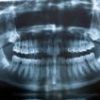

ОПТГ (ортопантомограмма) — это панорамный рентгеновский снимок обеих челюстей, зубных рядов, верхнечелюстных пазух, височно-нижнечелюстных суставов и нижнечелюстного нерва.

Это базовое исследование, которое позволяет врачу оценить общую картину и выявить скрытые проблемы, невидимые при стандартном осмотре.

На снимке наши специалисты видят не просто «белые и черные пятна», а сложную анатомическую структуру.

Врачи оценивают расположение и целостность зубов, равномерность костной ткани, состояние пломб и корневых каналов, а также выявляют малейшие отклонения от нормы.